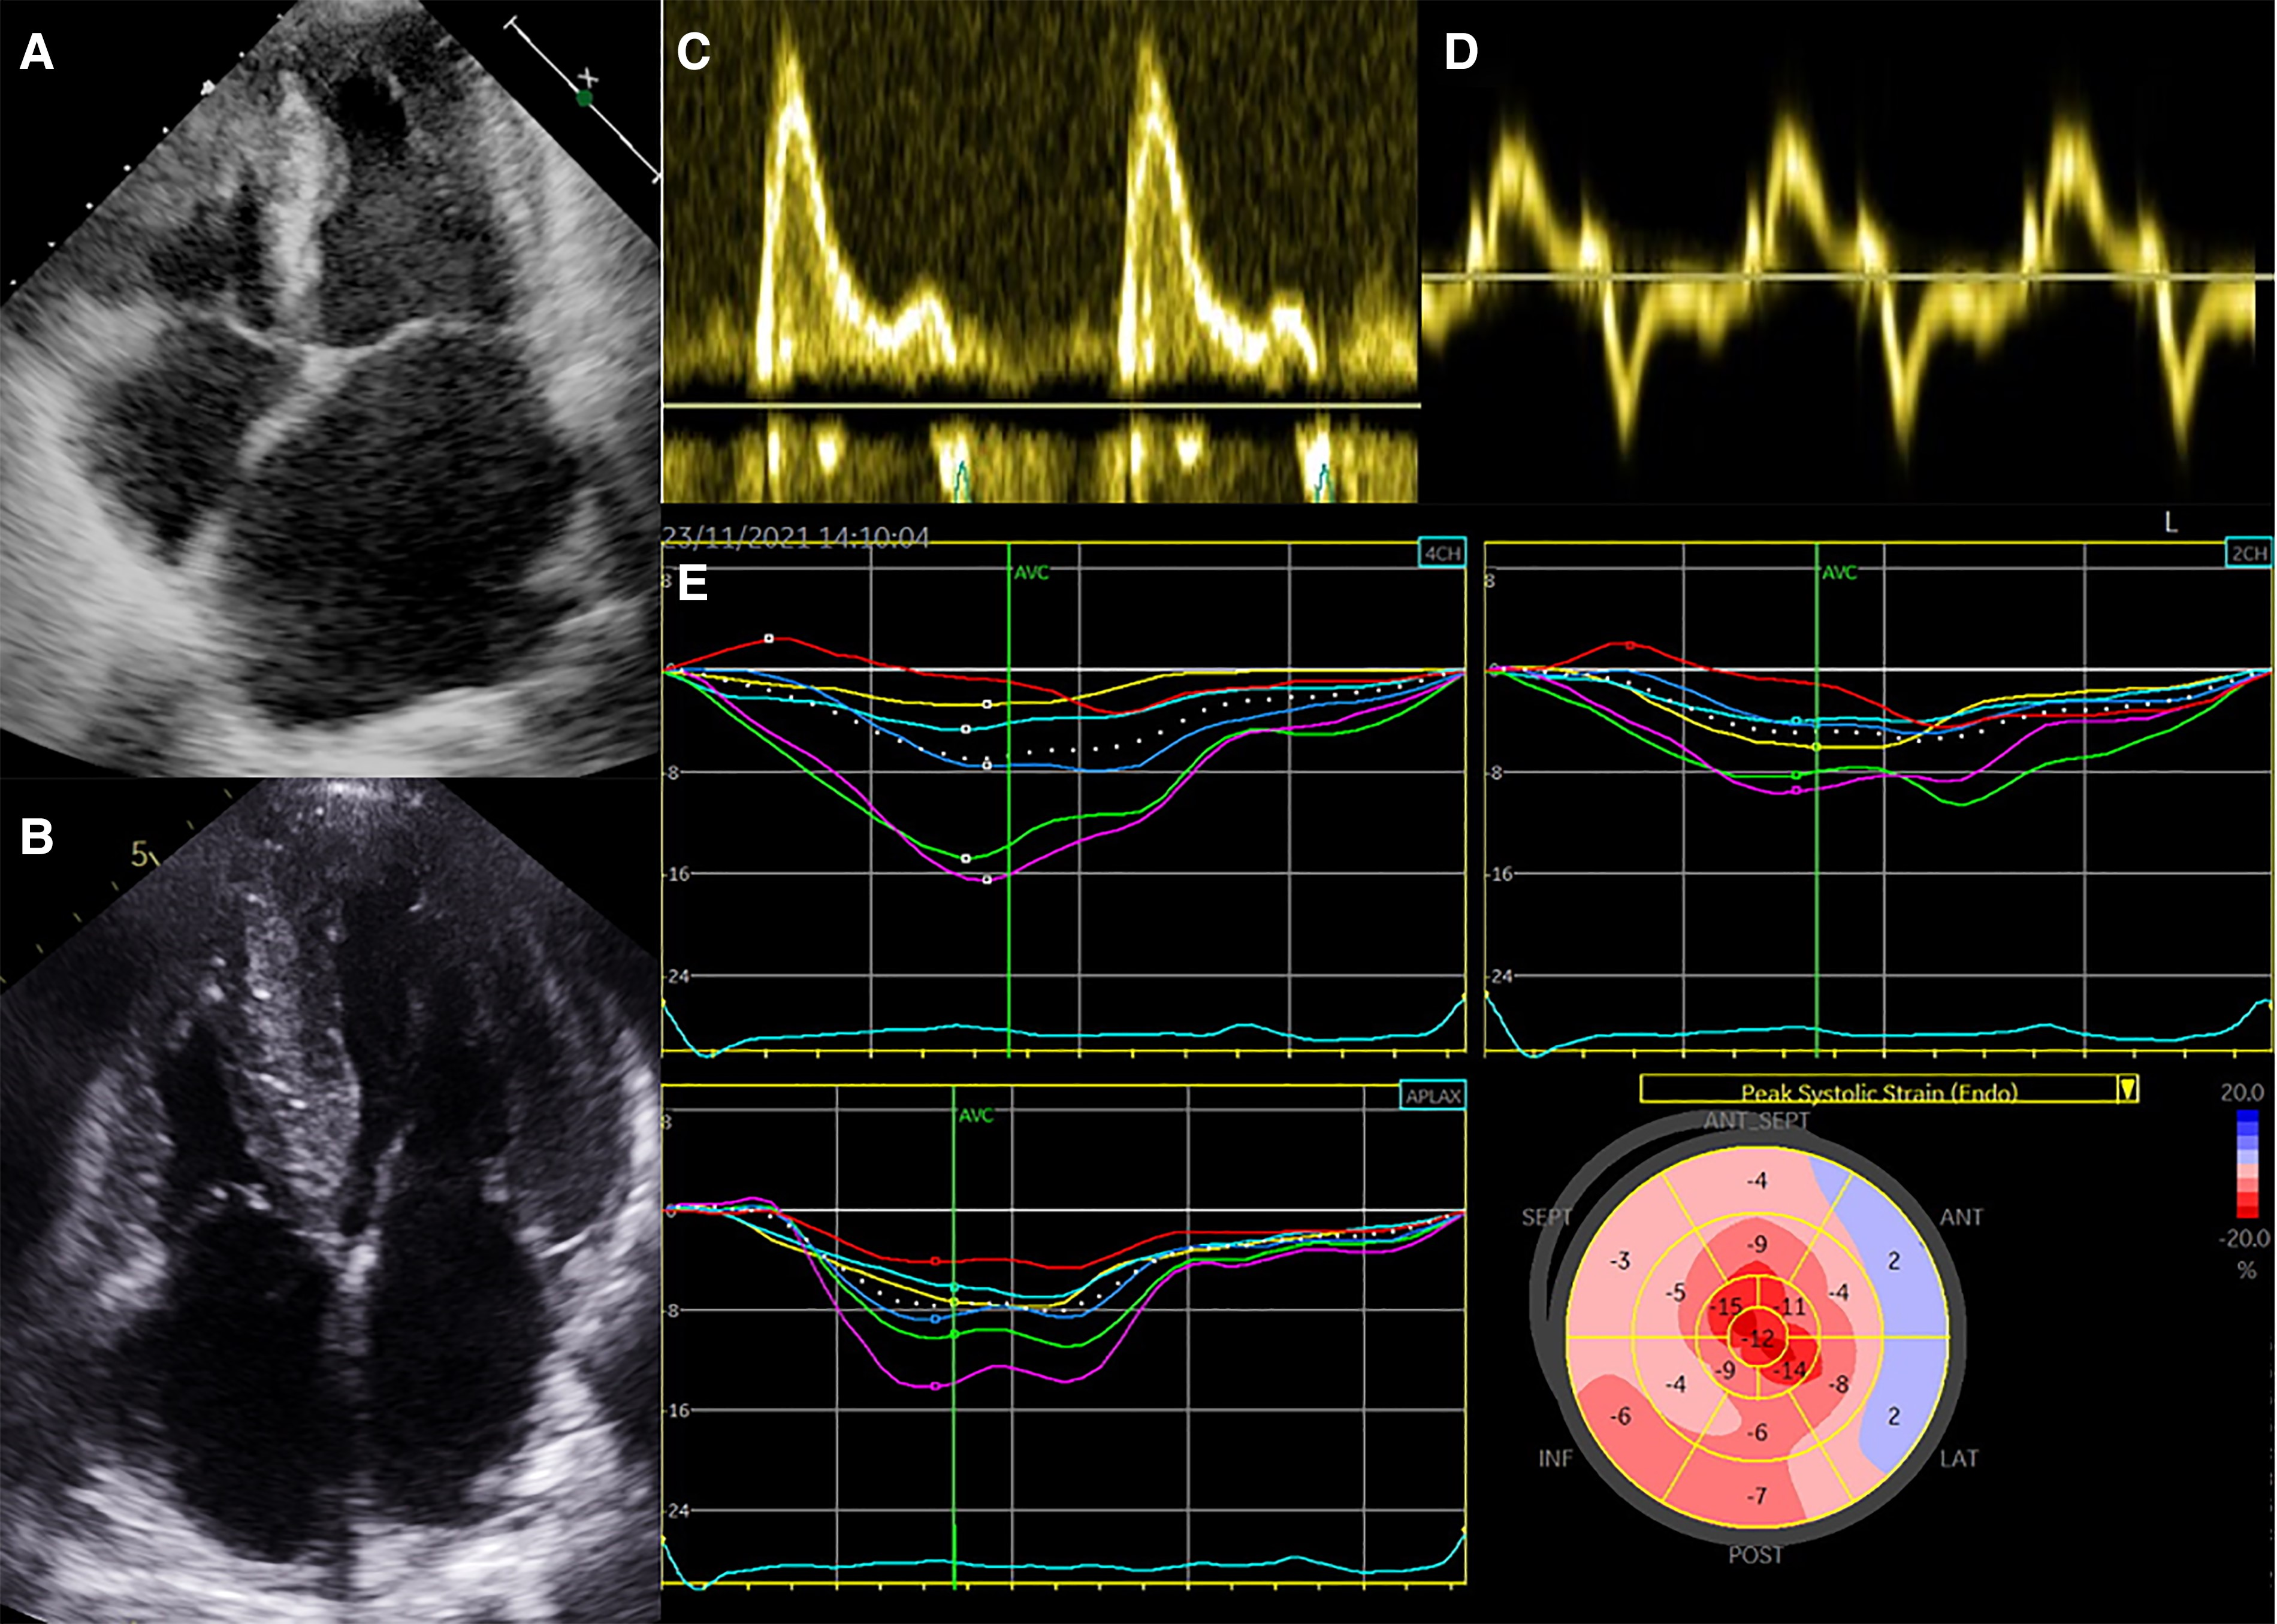

经胸超声心动图准确地描述了所有类型RCM共有的血流动力学特征:双心房扩大(不能归因于瓣膜疾病或AF等特定原因)、左心室和右心室射血分数正常或轻度降低以及非扩张性心室。多普勒成像可以显示限制性充盈模式,由于左心房(LA)压力升高,早期舒张充盈速度(E波)增加,由于心室舒张压升高,心房充盈速度(a波)降低,二尖瓣减速时间缩短,等容舒张时间缩短。组织多普勒通常显示舒张早期心肌速度(e′)降低,导致E/e′比值升高(图3)。

图3 限制性心肌病的超声心动图

注:(A)左心室腔体积小,壁厚明显增加,左心房扩张严重;(B)无肺动脉高压的双心室壁增厚;(C、D)限制性充盈模式,E/e′比值升高,与左心室充盈压升高一致;(E)心肌应变分析显示心脏淀粉样变性患者的心尖保留模式。